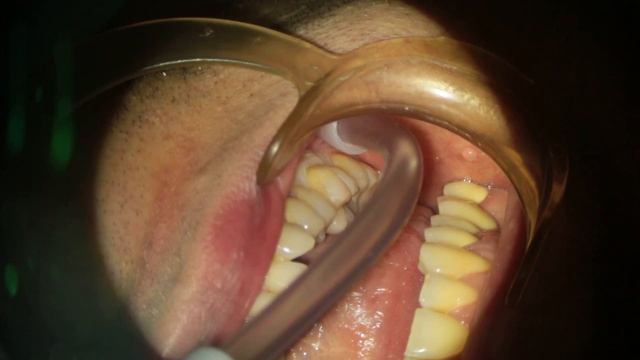

Интрасептальная анестезия.

Создадим вместе: интересные обучения 172 просмотров